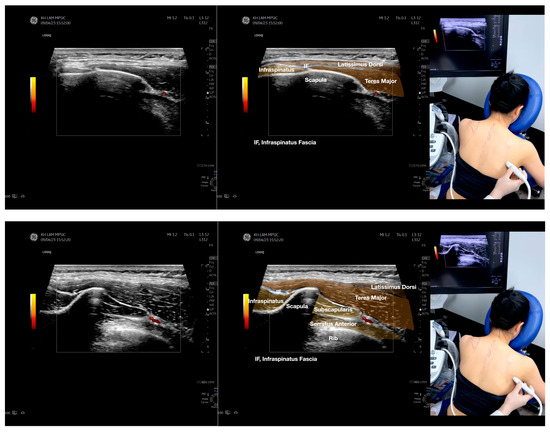

Figure 2.

Sonoanatomy of the lateral border of the inferior trapezius, its related muscles, and the infraspinatus fascia. The step-by-step scanning techniques of the structures illustrated in this figure have been shown in Video S6. Available online: https://www.dropbox.com/s/vjj49wiwdsidouz/Figure%202.docx?dl=0 (accessed on 1 January 2023). Dynamic ultrasound scanning of the anterior shoulder with the humerus externally rotated (palm up), elbow straight, and the shoulder actively flexed and abducted at about 90 to 100 degrees shows that the fibrotic and thickened bursa was noted to be snapping between the subscapularis tendon and the coracoacromial ligament, as shown in Video S3. The patient noticed this snapping during many of his daily activities with his shoulder flexed just above 90 degrees, e.g., taking off clothes and combing hair. Ultrasound-guided injection of the thickened and fibrotic bursa did not reproduce the usual pain nor reduce the pain, and it did not improve the shoulder snapping and flexion power with the elbow straight, shoulder flexed to 90°, and the humerus externally rotated (palm up). Ultrasound-guided injection of the cortical break reproduced the concordant pain and temporarily and partially reduced the pain with snapping and residual anterior shoulder pain (Video S4), but it did not change the snapping or weakness in the right shoulder flexion with the humerus in external rotation. With the failure of direct anterior treatment to the suspected lesions, it was essential to further explore other causes for the anterior painful snapping. Further detailed musculoskeletal examination of the scapular movement showed that the right scapulothoracic movements were not smooth compared to the left counterpart (Video S5) [4,5]. There might be some disruptions in the right infraspinatus fascia (IF) and its related muscles, including the lateral edge of the right inferior trapezius, rhomboid minor and major [6], teres major, latissimus dorsi [7,8] (LD), and posterior deltoid attachments to the IF [9,10]. Clinically, prominent and active trigger points were observed in the right infraspinatus muscle. Holding the inferior angle of the scapula, with the examiner’s fingers, especially over the origin of the teres major muscle over the scapula, the latissimus dorsi [11,12,13] and the scapular insertion of the rhomboid major muscle significantly improved the power of the resisted shoulder flexion with the elbow straight and the shoulder flexed to 90° with the humerus externally rotated (palm up). In order to illustrate the utilization of ultrasound-guided sonopalpation and ultrasound-guided digital palpation for detecting the suspected lesions of the IF and its related muscles, we presented the following videos (Videos S6–S9) and still images (Figure 2, Figure 3, Figure 4 and Figure 5) to demonstrate the essential techniques and crucial points of getting the normal sonoanatomy of the IF and its related structures. The gross anatomy of the IF and its related muscles were also shown in Figure 6, Figure 7 and Figure 8.